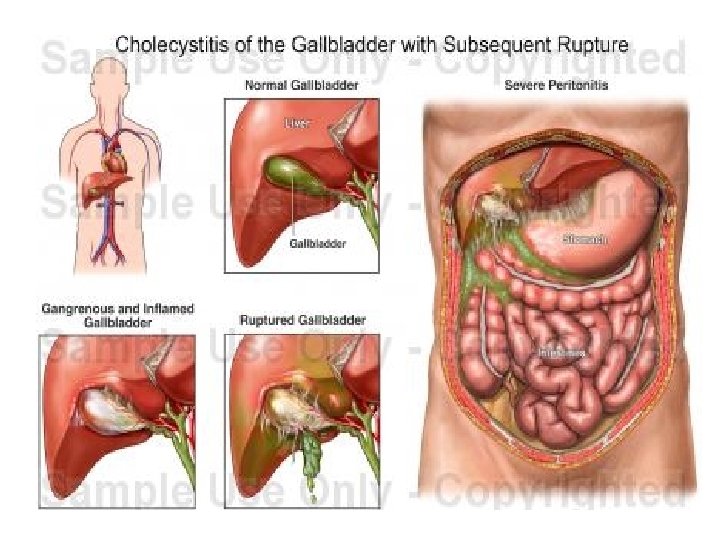

• KOMPLIKACIONET: - Kolecistit i supuruar (empiem i kolecistes) Perforim i kolecistes Pankreatit Kolangit Sepsis